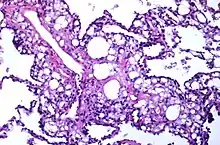

Numerous interstitial fat globules of varying size accompanied by inflammation and fibrosis is characteristic of chronic lipid pneumonia secondary to lipid aspiration.